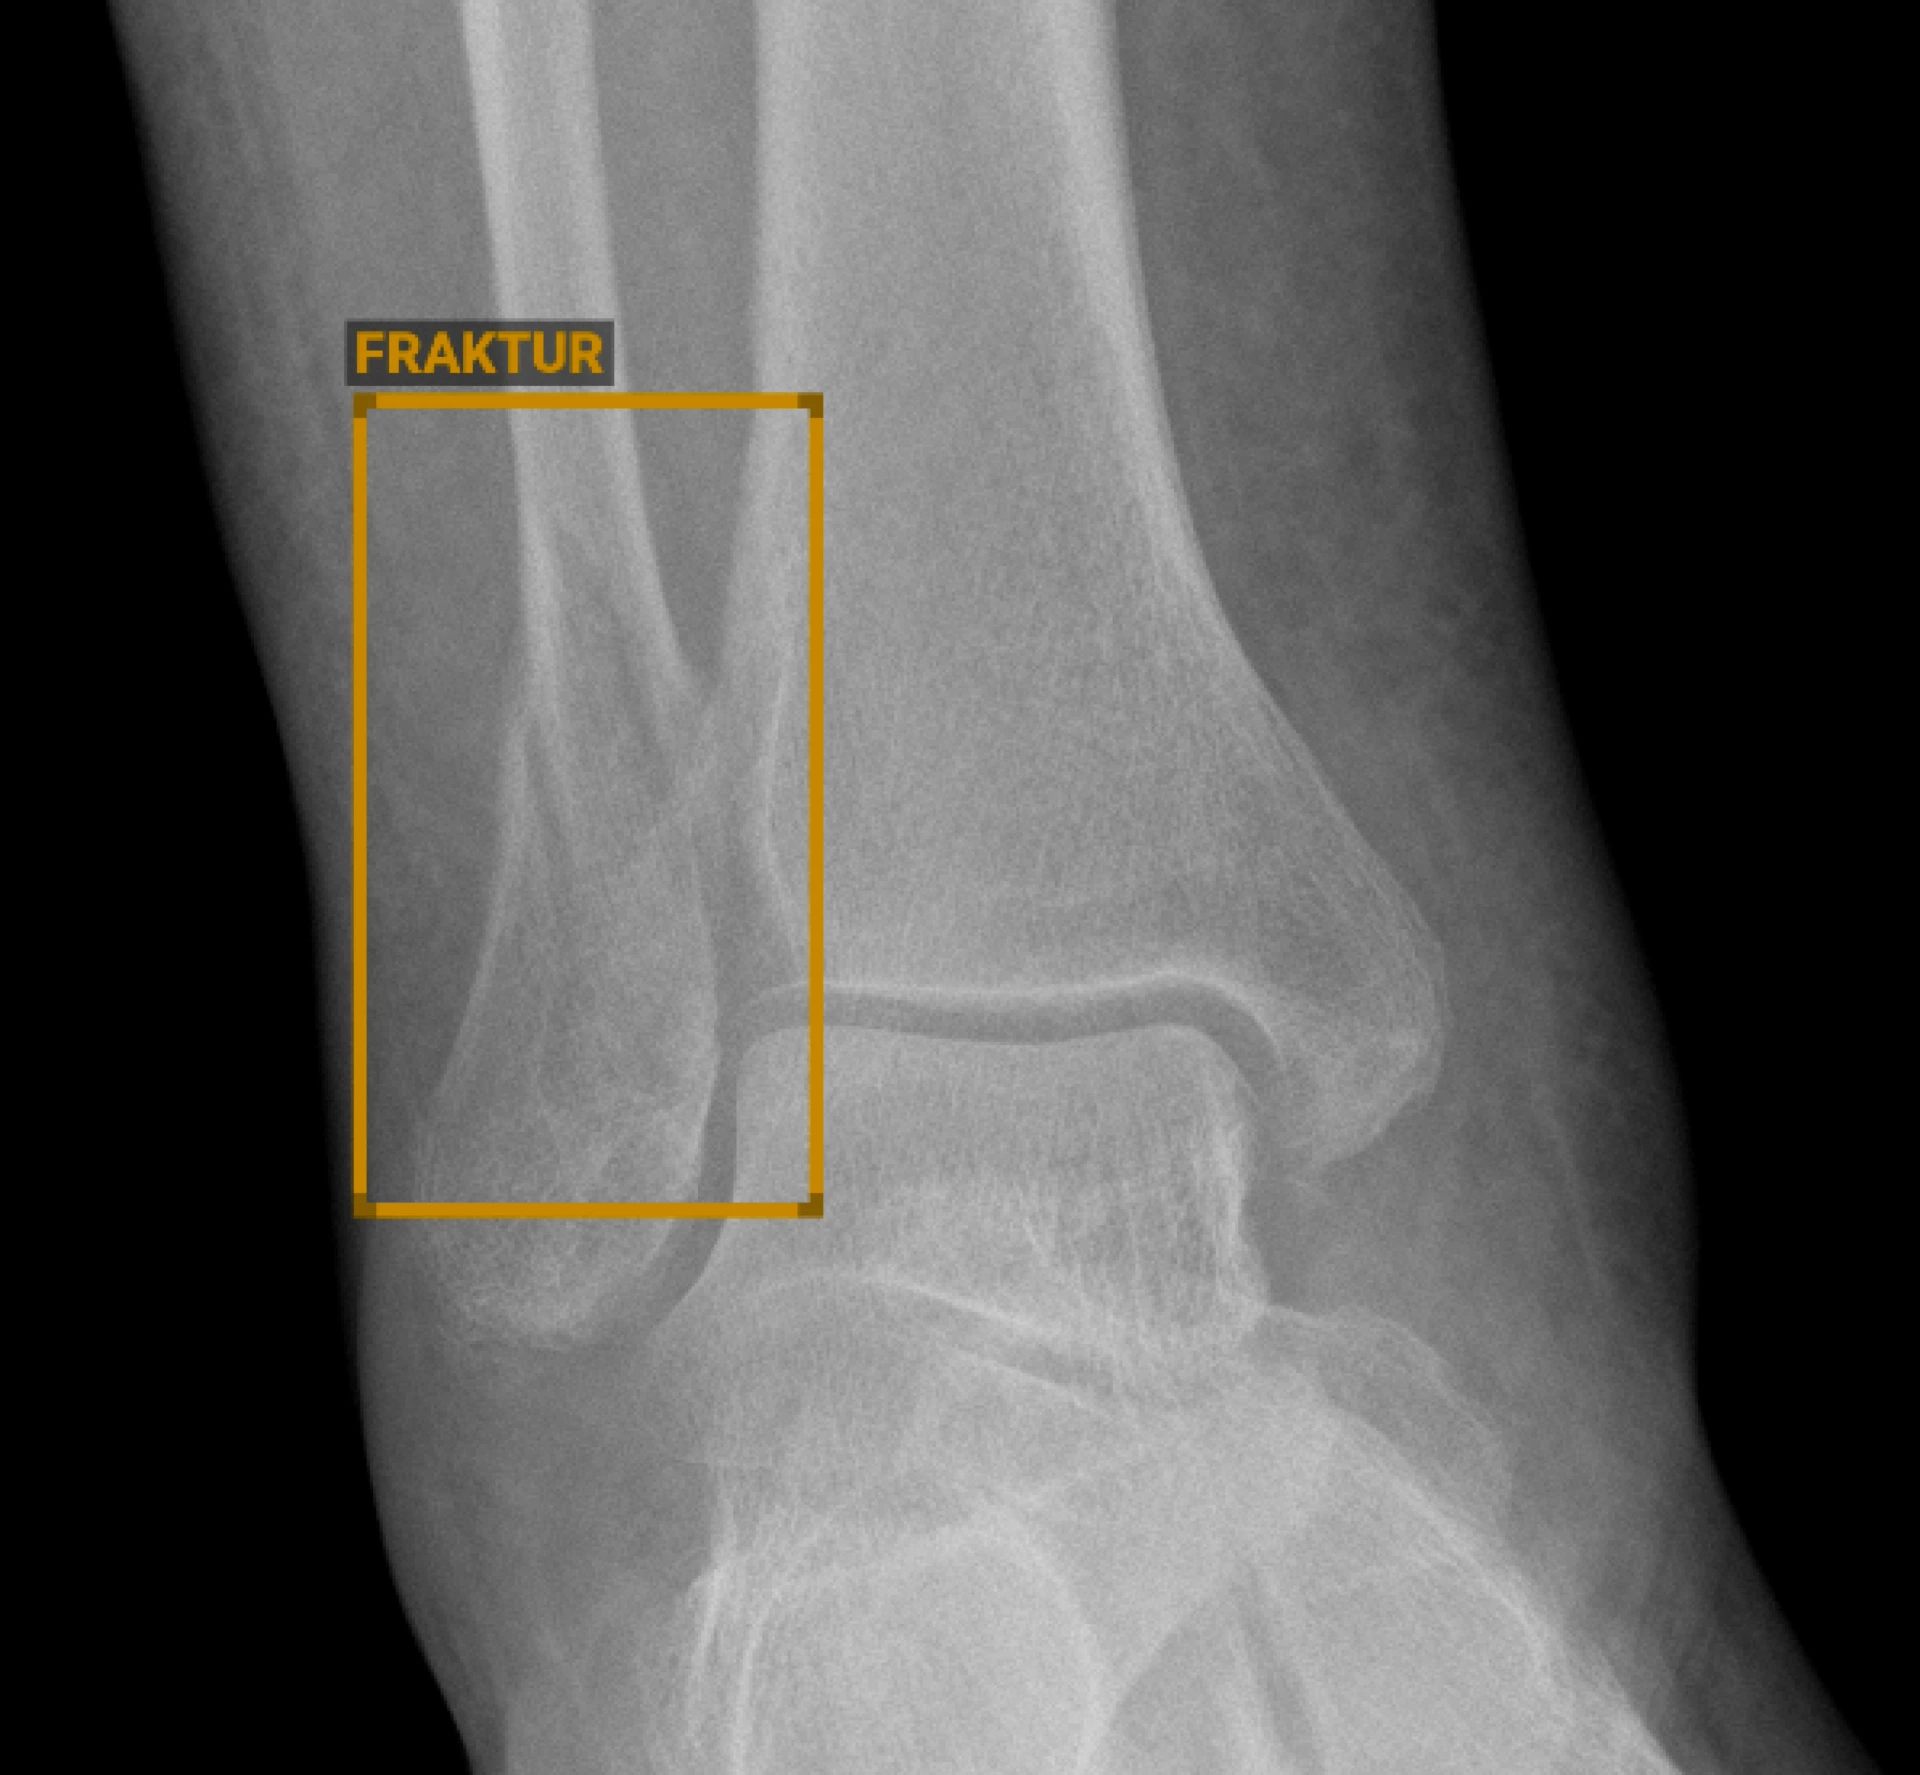

H: KI findet in der Radiologie bereits vielfach Anwendung, beispielsweise bei der Bilddatenrekonstruktion im MRT, oft ohne direkten Einfluss auf die ärztliche Bildbeurteilung. Mit BoneView von Gleamer ist auch die KI-basierte Entscheidungsunterstützung ein wichtiger Bestandteil unserer radiologischen Befundung geworden, insbesondere bei der Detektion von Frakturen auf konventionellen Röntgenaufnahmen. Durch den Einsatz dieser KI-gestützten Software gelingt es uns, die personellen Ressourcen optimal einzusetzen und gleichzeitig die diagnostische Genauigkeit zu verbessern. Die hohe Evidenzbasis von BoneView wird nicht nur durch unsere eigene laufende Validierungsstudie bestätigt, sondern auch durch zahlreiche hochrangige internationale Publikationen. So ermöglicht die KI eine zusätzliche Absicherung in der Diagnostik und verbessert spürbar die Effizienz und Qualität der Befundung, indem mögliche Frakturen automatisch erkannt und hervorgehoben werden. So können wir schneller eine präzise Diagnose stellen und unmittelbar die richtige Therapie einleiten. Insbesondere in der Akutversorgung verbessert die Software damit die Sicherheit und die Geschwindigkeit der Patientenversorgung erheblich. Eine weitere Anwendung ist die Detektion von Lungenrundherden mit einer CAD (Computerassistierte Detektion)-Software, die wir bereits seit vielen Jahren nutzen. Auch kleinere und „versteckt“ liegende Herde nah am Zwerchfell oder an Gefäßen werden hierdurch zuverlässig angezeigt. Auch hier erhöht sich die diagnostische Sicherheit vor allem bei hohem Patientendurchsatz, wie wir ihn in einem Haus der Supramaximalversorgung wie der UMM vorfinden. Für jeden Einsatz einer KI gilt jedoch, dass die korrekte Einordnung der Befunde weiterhin eine wichtige ärztliche Aufgabe zur Differenzierung echter Pathologien von falsch positiven Befunden ist. In der interventionellen Radiologie wird KI bereits eingesetzt, um Läsionen noch gezielter zu biopsieren, indem wir zur Biosieplanung Daten, beispielsweise aus der MRT-Bildgebung oder nuklearmedizinischen Untersuchungen, kombinieren und so besonders auffällige Anteile millimetergenau ansteuern können.

H: Insbesondere nachts im Schichtdienst sind wir häufig mit einer sehr hohen Arbeitsbelastung konfrontiert, während weniger Personal zur Verfügung steht und die Aufmerksamkeit gleichzeitig sinkt. In dieser Situation unterstützt uns die KI durch eine schnelle, objektive Analyse der Röntgenbilder und hilft dabei, Auffälligkeiten frühzeitig zu erkennen. Dadurch steigt die diagnostische Sicherheit deutlich, kritische Befunde werden priorisiert und die Fehleranfälligkeit sinkt. Auch bei der Befundung unter Zeitdruck ist die Unterstützung durch KI ein entscheidender Vorteil, um die Versorgung der Patienten auf einem konstant hohen Niveau zu gewährleisten.

H: Wir planen die vollständige Integration von KI-gestützter Software in unser neues Radiologie-Informationssystem (RIS) Siemens Syngo Carbon. Dadurch wird es möglich sein, die Detektionsergebnisse der KI direkt in unseren Befundungsworkflow einzubinden. Besonders wichtig ist dabei die geplante Funktion zur Workflowlisten-Priorisierung: Fälle, bei denen eine potenzielle Fraktur erkannt wird, können automatisch weiter oben auf der Befundliste erscheinen. Das bedeutet, dass dringliche Fälle schneller bearbeitet werden und eine rasche Therapieeinleitung ermöglicht wird – was insbesondere in der Notaufnahme einen direkten Einfluss auf das Therapiemanagement und die Verkürzung von Wartezeiten hat. Patienten mit unauffälliger Bildgebung können schneller entlassen werden.

KI wird ein unverzichtbarer Bestandteil der zukünftigen Radiologie sein. Systeme wie BoneView zeigen bereits heute eindrucksvoll, wie KI unsere Arbeit unterstützen und die Qualität der Patientenversorgung verbessern kann. KI wird repetitive Aufgaben übernehmen, uns bei der Priorisierung unterstützen und zusätzliche Sicherheit in der Diagnostik bieten.